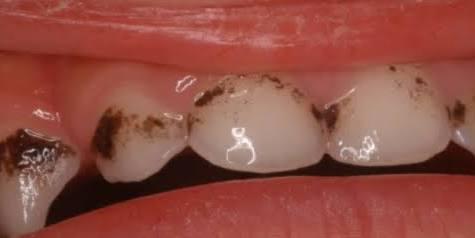

- 2025年11月27日 根っこが折れた!親知らずは移植できるか!?

こんにちは、静岡市清水区のわたなべミント歯科です。 さて、歯は一生物。出来るだけ多くを長く残していきたいものです。実際、歯が多く残っていて自分の歯で噛めている方の認知症や心臓疾患の罹患率は低いというエビデンスがあります。 … 続きを読む 根っこが折れた!親知らずは移植できるか!?